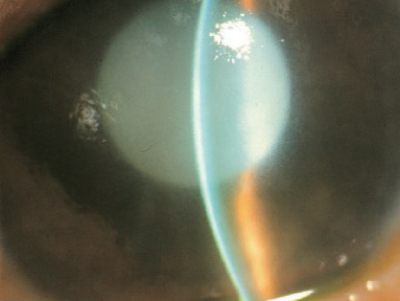

全身所見に異常を認めない。視力は右眼前手動弁、左 1.0。眼圧は右 53 mmHg、左 15 mmHg。右眼の眼底は透見不能である。右眼の前眼部写真を別に示す。